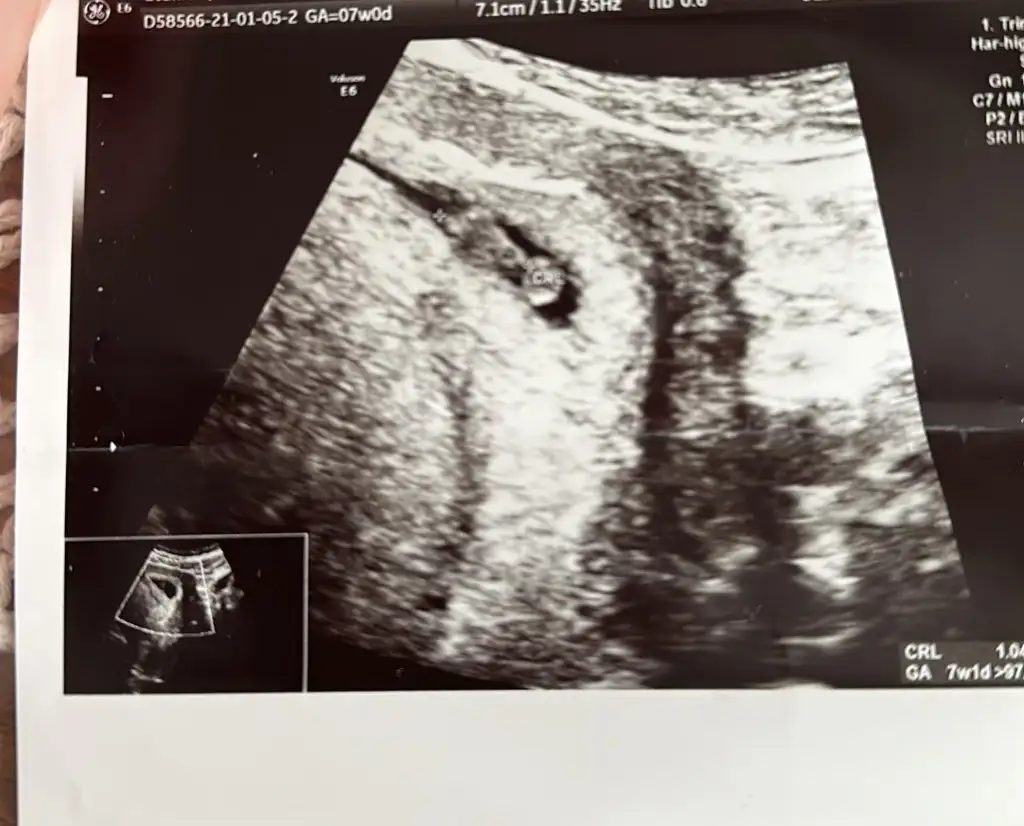

Arkadaşlar bugün 7+0 olduk haftasıyla uyumlu dedi. Var mı cinsiyet tahmin edebilen🙏🏻